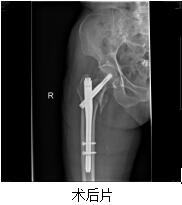

患者林某某,女性,100歲,秀嶼區(qū)東嶠鎮(zhèn)人,于2016-08-30在家摔倒,右髖部疼痛伴活動受限,不能站立及行走。于2016-08-31求診我院,急診擬“右股骨轉子間骨折”收住我院?;颊呒韧懈哐獕翰?、心臟病、慢支、肺氣腫等病史?;颊呷朐汉螅t(yī)院領導高度重視,組織心血管內科、呼吸內科、麻醉科等相關科室全院大會診,并制定詳細周密的診療計劃,決定予以行薇創(chuàng)骨折內固定術。完善相關術前準備后,于2016-09-02在麻醉下行右股骨轉子間骨折閉合復位PFNA內固定手術治療。手術時間才50分鐘左右,手術過程順利,術中出血少。術后di1天,患者右髖部疼痛已緩解明顯,可以自行床上翻身、坐起來,術后12天,患者康覆出院,成效滿意。

總之,老年人一旦摔倒出現(xiàn)髖部疼痛,千萬不要扶起站立,更不能行走,應聯(lián)系骨科醫(yī)生,或行必要的相關檢查(如拍片等),以防止進一步加重損傷。如為股骨轉子間骨折,閉合復位PFNA內固定具有薇創(chuàng)(切口?。?、出血少、創(chuàng)傷小、好的快等優(yōu)點,術后就可以早期床上活動雙下肢,骨折愈合后能下地較好,即便不能下地,在病床上活動也很好,就可以明顯降低老年人轉子間骨折的死亡率,重新下地走路也不再是單純的夢想!骨科又一次為百歲老人成功完成骨折手術,再一次體現(xiàn)了我院的綜合實力!